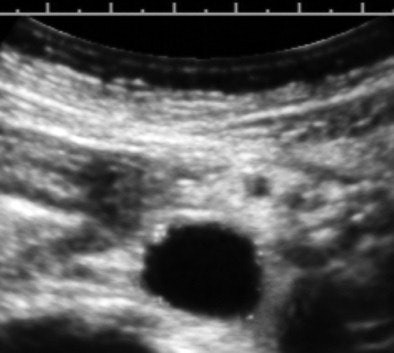

Here's a routine practice example that demonstrates the value of a medically centered exam technique. The image below is from the exam of an overtly healthy 47-year-old woman referred for heavy menstrual flow.

The image is a transverse cross-section of the distal abdominal aorta about 2 cm above the bifurcation. There are subintimal calcifications and a small plaque, which are distinctly pathologic, but now fairly common "incidental" findings at this woman's age.

Let's start with the way that we search for and perceive reflectivity, such as plaques or calcifications in the wall of a vessel. This is a contrast resolution task, which is identical to searching for a breast mass or looking for signs of placental senescence. Actually, contrast resolution search tasks are part of nearly all ultrasound exams.

For any instrument settings and inherent noise factors, contrast anomalies are best seen as cross-correlations between serial image planes (i.e., watching the screen while the probe is translated or scanned across the region of interest). This concept is really important, as it emphasizes that the exploratory ultrasound exam should be conducted as a live scanning survey. Once pathology is found, technical factors are optimized for the best possible still or representative image.

In this case, a small extension to the exam resulted in confirmation of an abnormal lipid profile and the initiation of aspirin and statins. By being informed of the finding, the patient has motivation for the behavioral changes that will presumably have a major impact on her life span. As for the bleeding, that was a simple polyp.

Logically, if an exam is done to exclude a major problem in one area, is it supportable that we not use the opportunity to evaluate problems that have high prevalence in the patient population, that are easily sought by ultrasound, and which have definite ultrasound findings? A very narrow clinical focus is a little like doing a chest x-ray and only looking at the right middle lobe of the lung and neglecting everything else. Scanning through the distal aorta probably adds 30 seconds to a pelvic ultrasound exam, hardly any time at all.